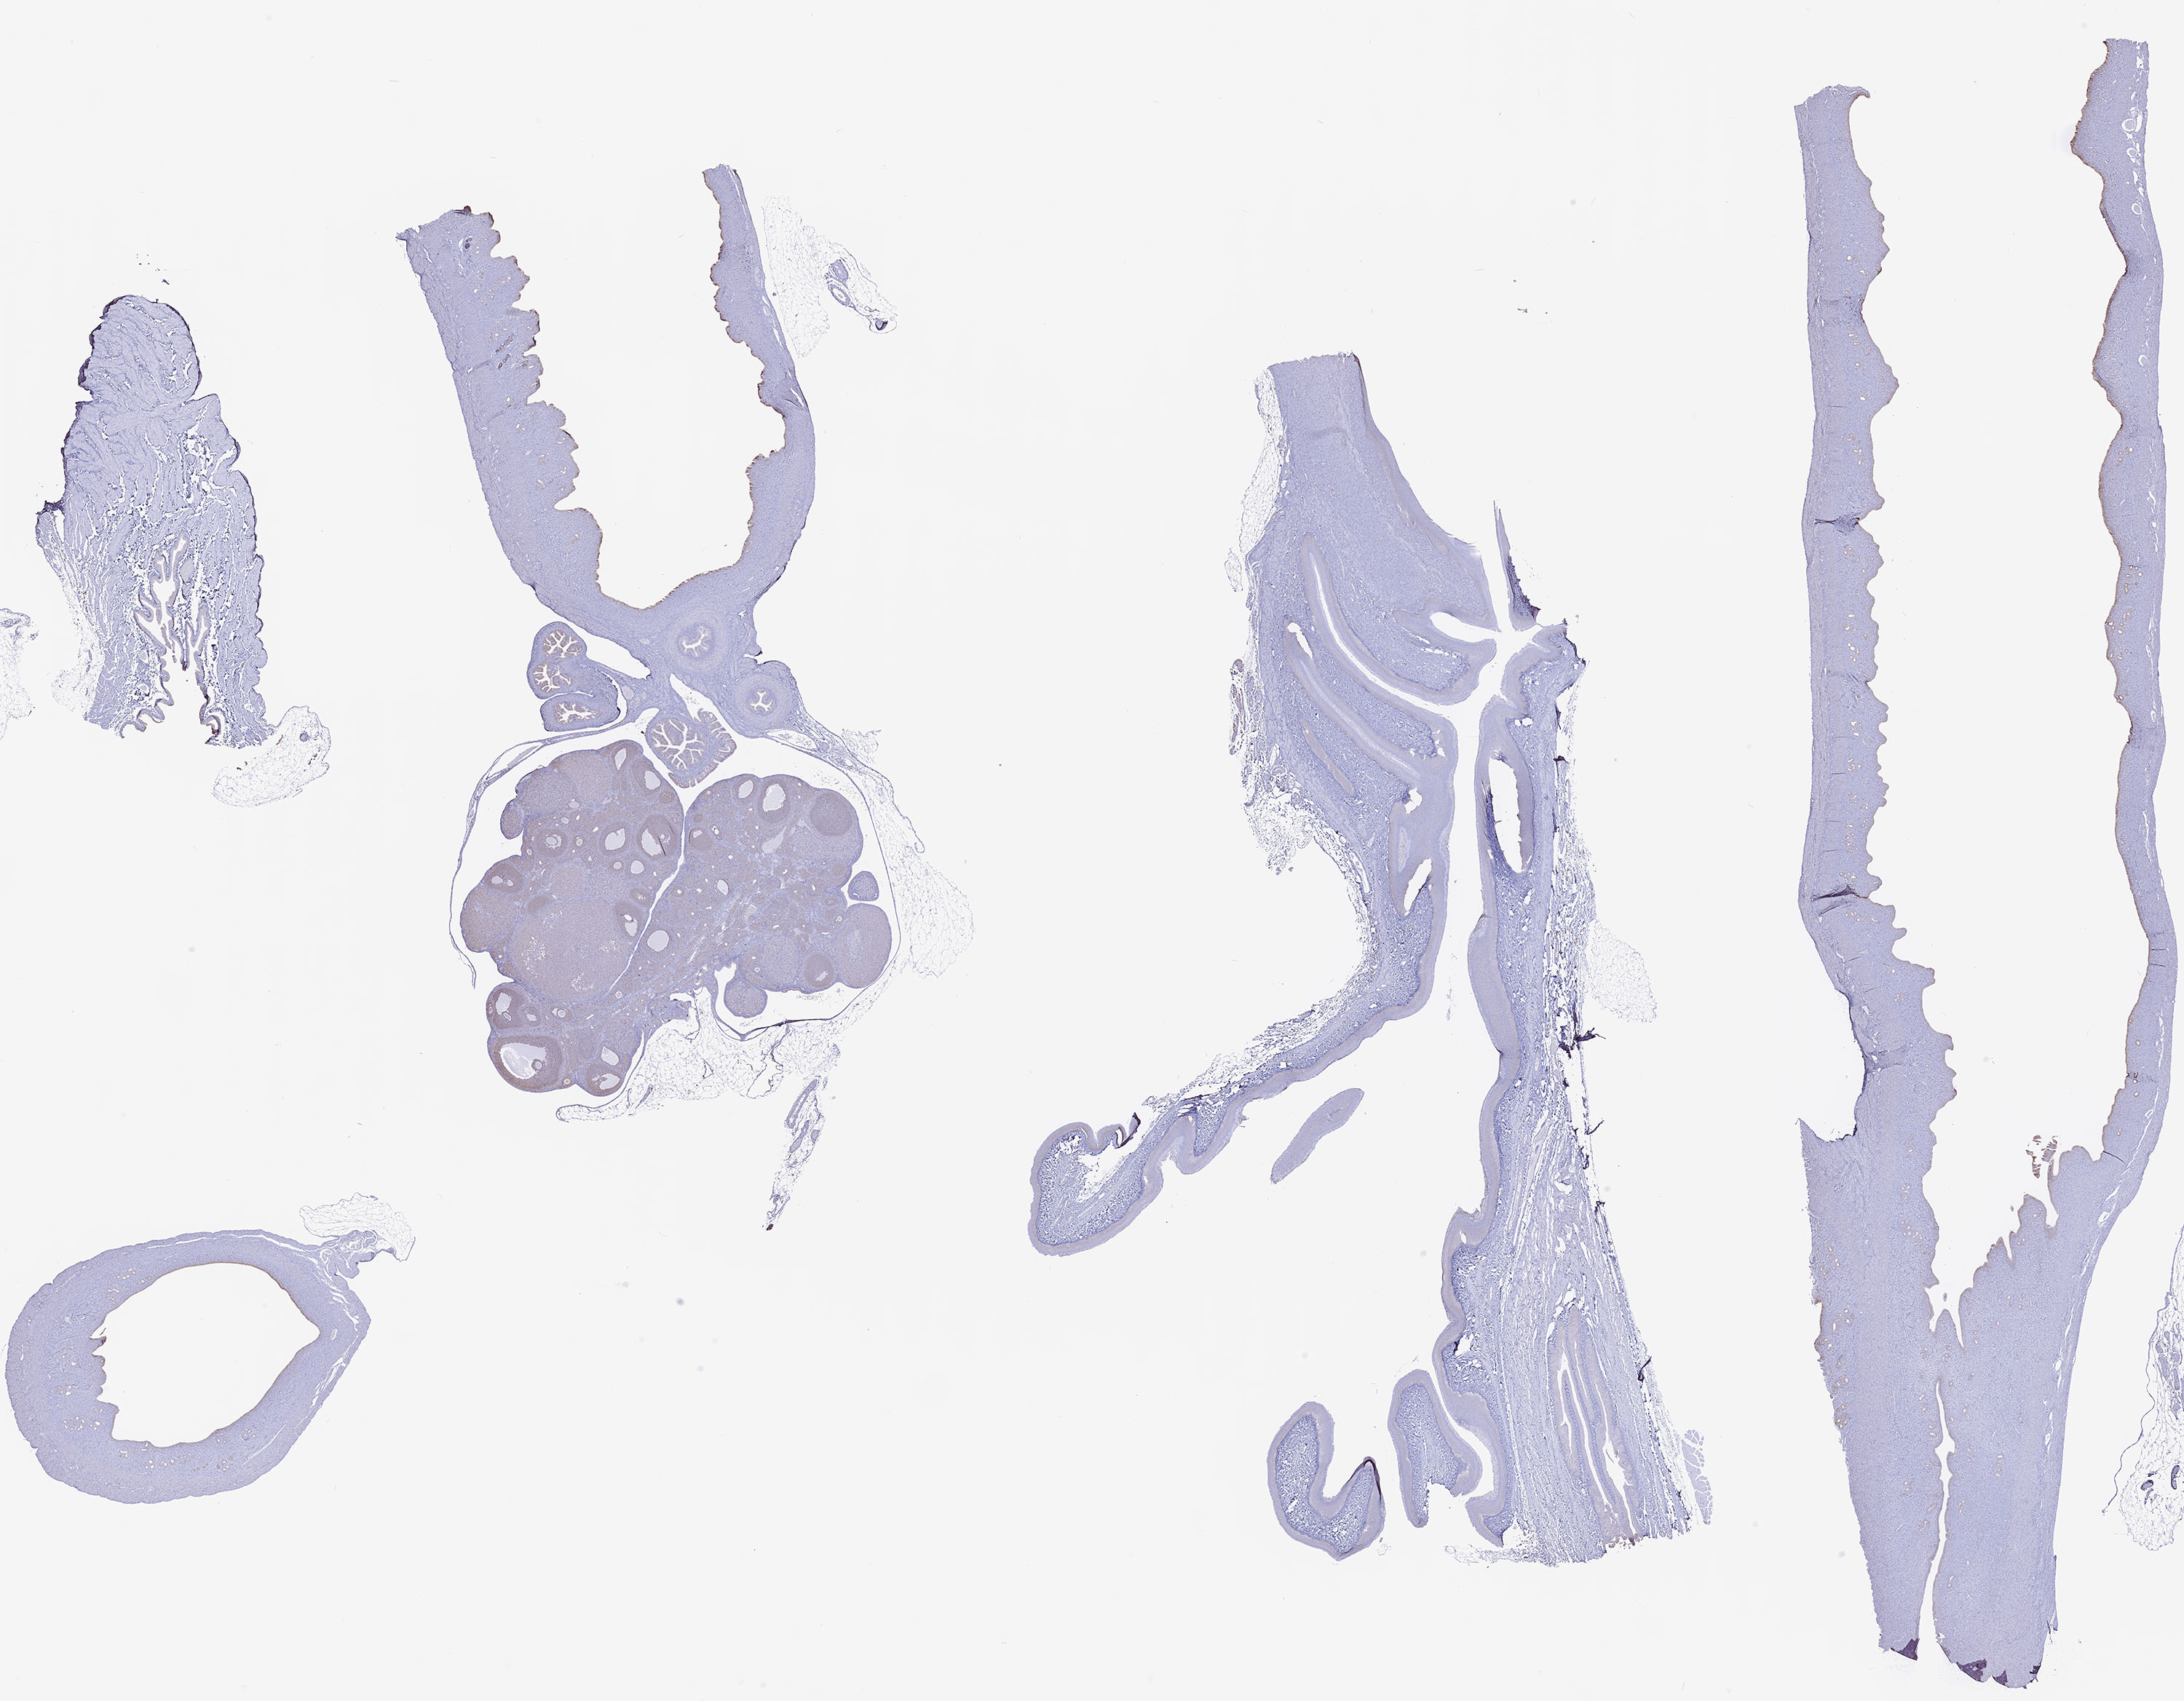

Estrogen Receptor Beta Estrogen Receptor Beta: Download a high resolution copy of the Estrogen Receptor Beta image.